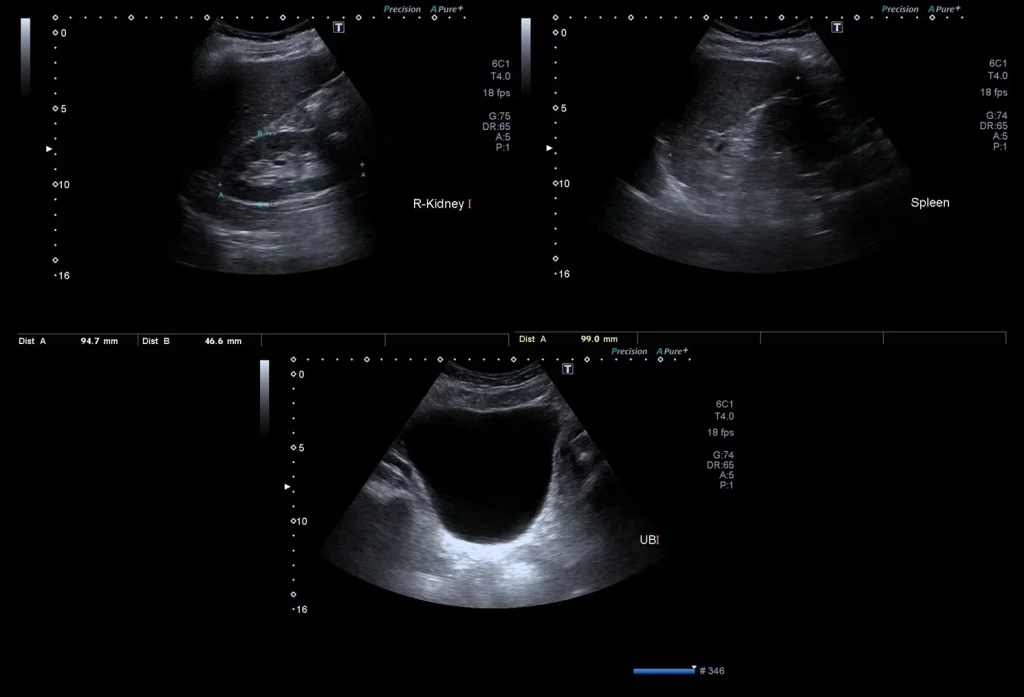

An abdominal ultrasound is a non-invasive medical procedure.

Used to create images of the organs inside your abdomen.

Including the liver, gallbladder, spleen, pancreas, and kidneys.

It’s a valuable diagnostic tool that can help identify.

A variety of medical conditions and is widely available in Dubai’s healthcare facilities.